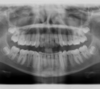

Vues avant le traitement